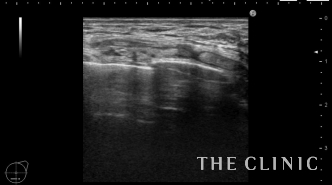

一部に壊死脂肪が残りましたが、しこりは触れなくなりました。

大胸筋下のしこりは皮下、乳腺下のしこりに比べると難易度が高いと思います。